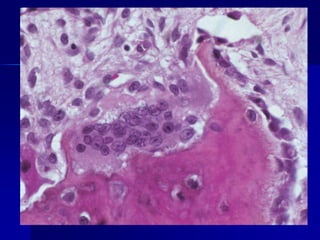

Condrosarcoma	Definición: tumor maligno de condroblastos, varón>mujer; edad 30-60	Etiología: el tumor surge e novo o secundario a un condrosarcomapreexistente,exostosis o enfermedad de Paget.	Clínica : crecimiento de la masa con dolor y edema.	Típicamente involucra la pelvis ósea, columna y hombros	Micro: compuesto de condrocitos atípicos y condroblastos, frecuentemente con núcleos múltiples en una laguna.

Condrosarcoma Definición: tumor malignode condroblastos, varón>mujer; edad 30-60 Etiología: el tumor surge e novo o secundario a un condrosarcomapreexistente,exostosis o enfermedad de Paget. Clínica : crecimiento de la masa con dolor y edema. Típicamente involucra la pelvis ósea, columna y hombros Micro: compuesto de condrocitos atípicos y condroblastos, frecuentemente con núcleos múltiples en una laguna.